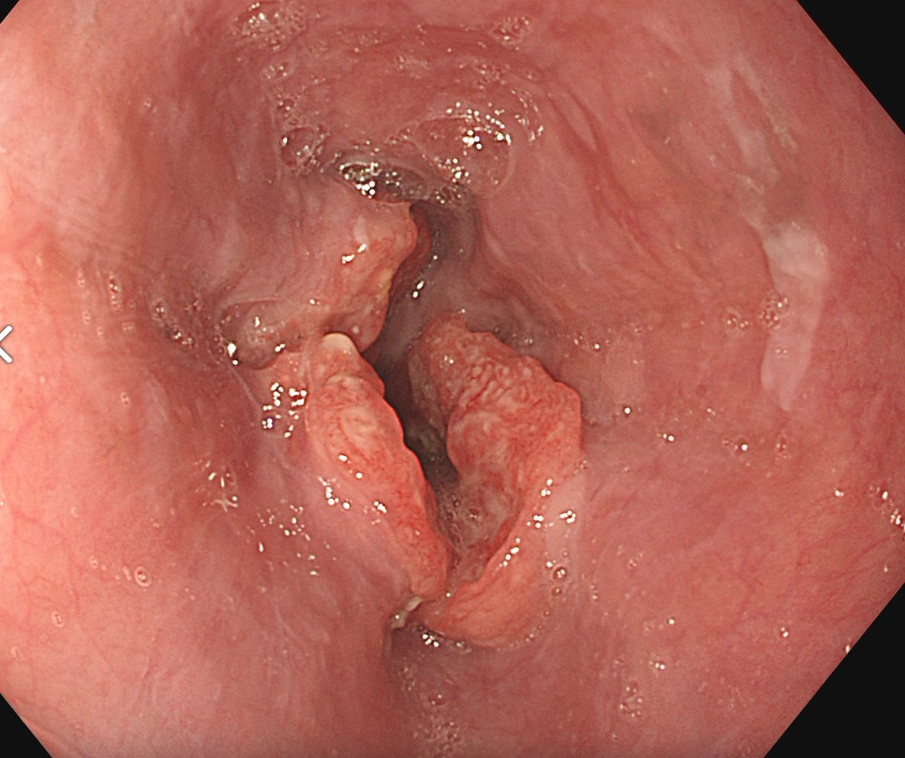

食道がんの検査は、がんかどうかを確定するための検査と確定された後に行う進行度を判断するための検査があります。まず確定するための検査としては、内視鏡(胃カメラ)で直接病変を観察する内視鏡検査が行われます。内視鏡で異常がみられる場合は組織を採取し、顕微鏡で観察する生検を行い診断が確定されます。

内視鏡(胃カメラ)画像